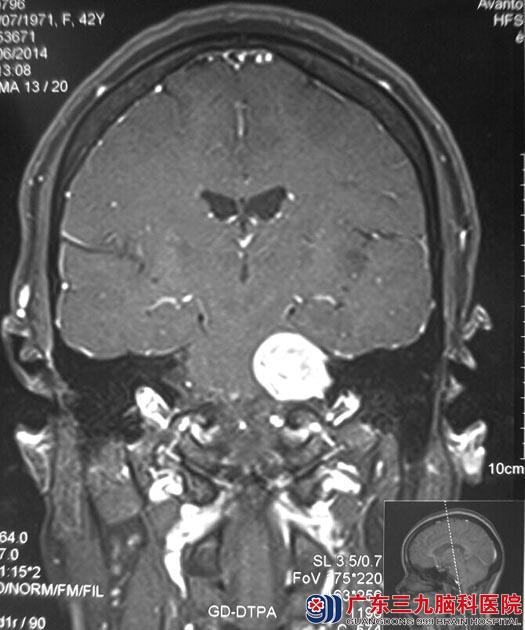

广东三九脑科医院头颅MRI检查提示左侧桥小脑角区示一圆丘状占位,大小约3.09cm×2.27cm×2.82cm,考虑神经鞘瘤可能性大,综合神经外科鲁明主任建议行手术切除治疗。

全麻下行左侧桥小脑角占位病变切除术,显微镜下见肉红色肿瘤组织,包膜完整,被小脑前下动脉包绕,质中,血供丰富,肿瘤与面听神经及脑干粘连明显,予分离后行肿瘤全切,术中对三叉神经、面神经、听神经、脑干均保护完好。手术后周女士耳鸣症状较前好转、康复出院。术后病理结果:听神经瘤。

手术前